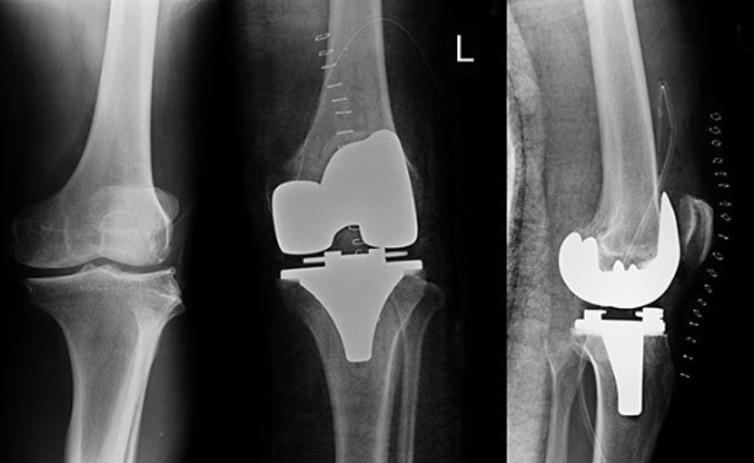

Joint Replacement Surgery (Hip & Knee)

Replacing damaged joints to restore function and alleviate pain.

What is Joint Replacement Surgery?

Replacement of a damaged joint with an artificial one made of metal, ceramic, or plastic.

How is Joint Replacement Surgery Performed?

The damaged joint is removed and replaced with a prosthesis fixed securely to allow smooth movement.